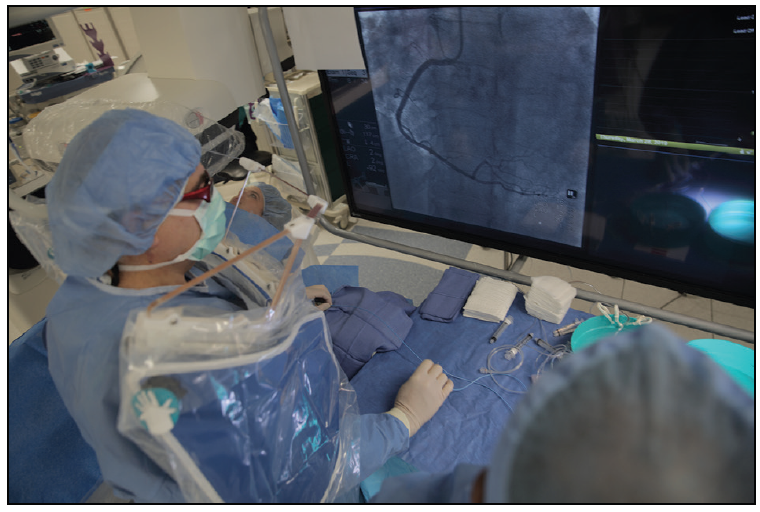

The left radial artery access technique involves conventional placement of the patient on the catheterization laboratory table. The left arm is abducted 90° from the body and the hand is laid prone (Figure 1). A preparation table of similar height is positioned distal to the arm for preparing balloons, catheters, and stents. This approach emphasizes coaxial movement of catheters to the coronary arteries and left ventricle. The operator stands on the caudal side of the extended left arm. The fluoroscopic and hemodynamic monitors are in front of the operator so that he or she is standing directly in front of the screens. There is no torsion on the operator’s body, and he or she is looking forward at the monitors (Figure 2).

A catheterization technologist stands on the patient‘s right side and controls the table during the procedure using an additional monitor. A scrub technician stands to the right of the operator and prepares the equipment. One nurse circulates. An additional technician monitors hemodynamics and enters the patient’s chronologic data.

The operator stands behind 800 lb of lead from the Zero-Gravity suspended radiation protection system (Biotronik, Inc.), which also protects the operator’s head from radiation. The catheterization technician assistant also benefits from the Zero-Gravity radiation protection, which is positioned to the left of him or her (Figure 3). Real-time radiation sensors (RaySafe; Unfors RaySafe AB, a Fluke Biomedical company) are employed throughout the case. Access and closure with use of the Vasc Band hemostat (Teleflex) at the access site are accomplished without repositioning the arm.